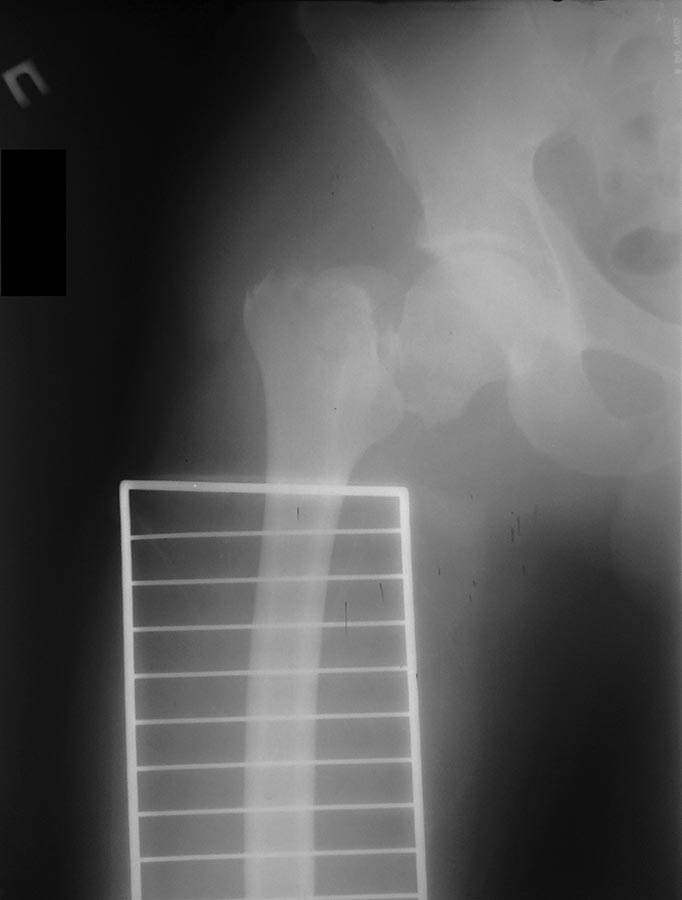

Пока надо делать снимки в классических укладках, т.е. хотя бы в двух проекциях. А по тактике из всех переломов: шейка является приоритетным и ургентным. Идеально фиксировать канюлированными винтами, но усложняется тем, что имеется перелом верхушки вертела. Навряд ли получится закрыто, надо открывать. Все зависит от возможностей на месте (писали насчет DHS), можно и интрамедуллярный гвоздь, но не надо укорачивать, только пустить overlapping, т.е. пластина от DHS покрывает часть гвоздя.

В фиксации тибиал плато надо соблюдать осторожность, потому что по снимку кажется поврежденной только медиальная часть, и медиальные переломы имеют тенденцию вовлечения задней поверхности плато. Боковой снимок покажет, куда идет линия перелома, а также покажет состояние перелома надколенника. Фиксировать надо buttress-опорной пластиной иначе винты не удержат варусный коллапс. В зависимости от вовлечения разгибательного механизма фиксация надколенника.

Здесь выставлен ренгенограммы больного, ему 21, травму получил в результате высокоскоростной погони на украденной машине, которая закончилась смертью трех остальных “боевых комрадов”. Начатую коллегой открытую операцию на шейке пришлось закончить мне, установкой винтов и ретроградной фиксацией бедра. Выписка в обычное сроки и наблюдался амбулаторно. Каждый раз напоминали о возможности осложнений ввиде несращения! По истечению 4 месяцев появились признаки варусной деформации. На СТ срезах несращение шейки и бедра. Риминг, замена на более толстый гвоздь и вальгусная остеотомия.